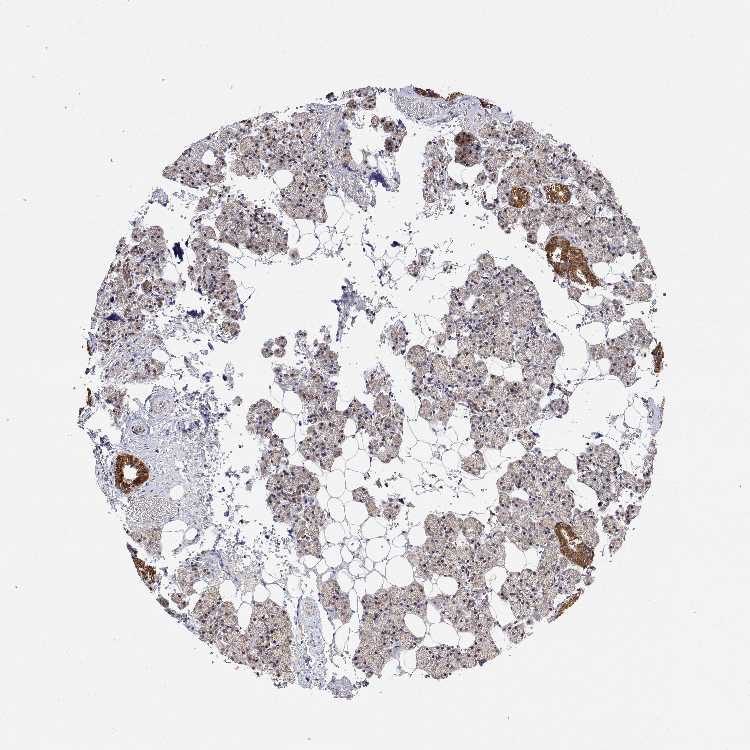

SALIVARY GLAND - Antibody stainingi

Antibody staining in the annotated cell types in the current human tissue is reported as not detected, low, medium, or high, based on conventional immunohistochemistry profiling in selected tissues. This score is based on the combination of the staining intensity and fraction of stained cells.

Each image is clickable and will lead to virtual microscopy that enables deeper exploration of all samples and also displays staining intensity scores, fraction scores and subcellular localization as well as patient and tissue information for each sample.

Antibody HPA065048

Glandular cells High